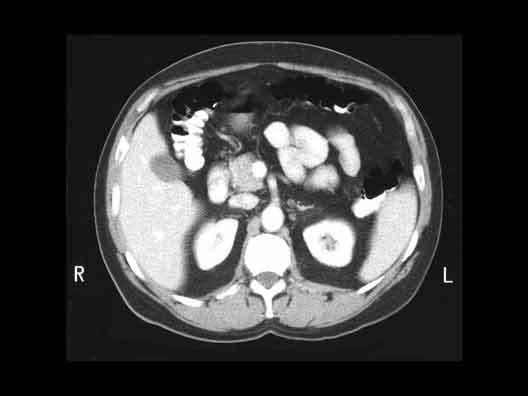

Superior Mesenteric Artery

1. Liver

2. Gall Bladder

3. Colon

4. Small Bowel

5. Superior Mesenteric Artery

6. Aorta

7. Spleen

8. Left Kidney

9. Right Kidney

10. Inferior Vena Cava